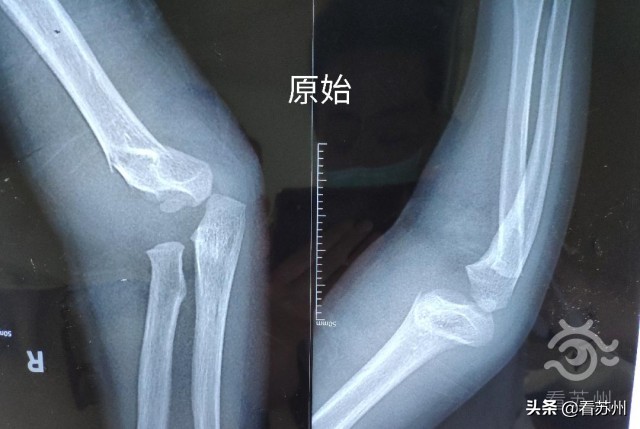

瑶瑶的父母立即将她送入当地医院就诊,确诊为肱骨髁上骨折,医生进行复位未成功,反而造成旋转移位,医生建议手术。

苏州市中医医院骨伤科副主任中医师尤君怡仔细查看了瑶瑶的CT片及右上臂的情况,发现瑶瑶的肘部旋转移位明显,常规的处理方式是手术切开复位和内固定治疗,但该治疗方案创伤大,难免会遗留疤痕。

经过详细分析和评估,尤君怡认为,可采用中医传统的手法复位治疗。在常规清毒处理后,尤君怡利用吴门医派正骨法的独特技术进行了手法复位,贴上医院特制的膏药,再用木夹板固定、绷带包扎,10分钟便完成了。复查CT显示,骨折已完全复位。